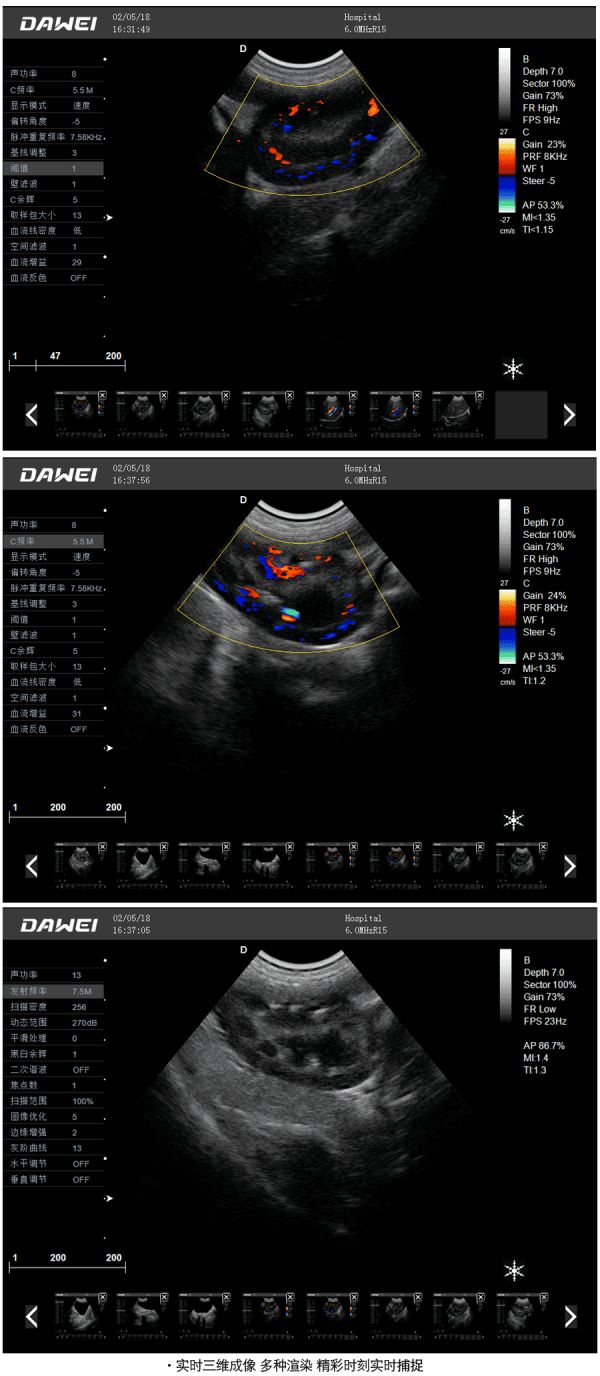

宠物多普勒彩超临床图像:

● 实时三维成像 多种渲染 精彩时刻实时捕捉